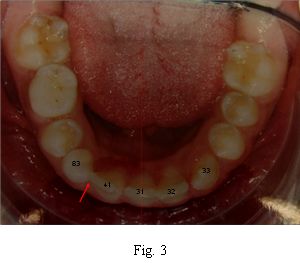

Se le realiza una completa historia clínica. Es una paciente sana desde el punto de vista general y regional, presentando alteraciones al examen clínico local. Se observa dentición mixta tardía, ausencia del órgano dentario permanente 4.2, persistencia del 8.3 y pérdida del equilibrio oclusal con desvío de línea media inferior a la derecha (Fig 2), por pérdida prematura del 8.2, contactando el 4.1 con el 8.3. No se observan ni se palpan alteraciones óseas en la zona. Presenta pequeños diastemas en el sector ánteroinferior que generan unos 3 mm de discrepancia dentaria positiva, insuficiente para ubicar el diente faltante (Fig. 3). La relación molar sagital es de clase II de Angle derecha e izquierda (Figs. 4 y 5), con falta de espacio suficiente para la erupción y correcta ubicación del 1.3 (Fig. 4).

Fig. 3 Pequeños diastemas, insuficientes para generar el espacio necesario para el 4.2